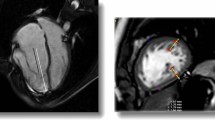

On CMR images, LGE was identified in 30/107 (28%) of EA patients, mainly occurred at subendocardium of the RV and/or basal and middle septum (Fig. 2). The EA with ASD group had a higher incidence of LGE than the EA without ASD group (52% vs. 18%, p < 0.05).